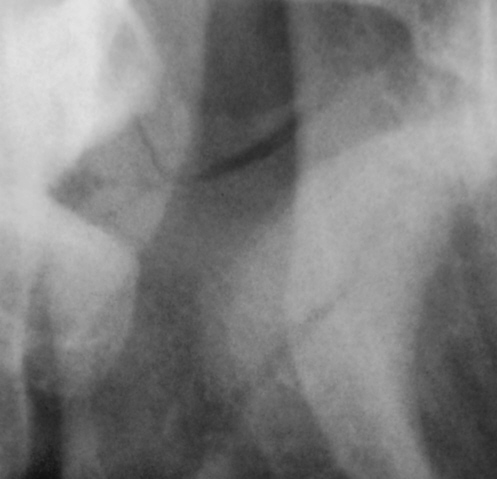

Вот один из них.

Валентин Львович! Результат налицо. Открытый перелом в области 8-го зуба. И на противоположной стороне в области 2-3-го зубов.

Переломы: через лунку 8 с одной стороны, с другой - в обл 3/4.

Замечания: не маркирована сторона, не достаточно косой снимок - наложение сторон. Стоило снять с двух сторон.